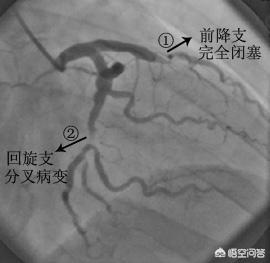

- 造影剤は冠動脈を "照らす":人体の冠動脈は比較的小さく、冠動脈の主幹はわずか5、6ミリ、太い枝の一部は2、3ミリ程度、残りはさらに細い枝で、これらの血管は周囲の組織とつながっており、その手前は骨や筋肉などで覆われている。そこで、冠動脈造影を行う際には、先ほどのカテーテルの中から造影剤を注入し、冠動脈を造影剤で満たします。造影剤はX線不透過性の薬剤で、冠動脈造影の際に冠動脈を "明るく "照らし、冠動脈の分布、大きさ、狭窄や閉塞の有無をはっきり見ることができる。

- DSA(Digital Subtraction Angiography)とは血管を撮影するカメラである:先に述べた冠動脈の写真を撮るための装置がDSAであるが、実はこれもX線検査の一種であり、造影剤を注入しながら様々な冠動脈を多角的に、まさに360度の死角とも言える角度から写真や動画を撮影・記録することができ、これらの写真や動画はCD-ROMに預けることができるので保存や解析が容易である。冠動脈造影が冠動脈疾患を診断するためのゴールドスタンダードであるのは、冠動脈造影がこれほど鮮明な写真やビデオを撮ることができるからである。

冠動脈造影検査は、大腿動脈の位置から針を刺し、冠動脈の位置までチューブを通し、ヨード造影剤を打ち込んで冠動脈を映し出し、冠動脈の先天性疾患、アテローム性動脈硬化症、動脈瘤、動脈奇形などを診断するもので、その多くは内腔の狭窄をもたらすアテローム性動脈硬化症である。狭窄の程度を評価することができ、心筋梗塞を伴う重度の狭窄の場合は、治療目的で狭窄した内腔を広げて血流を回復させるためにステントを直接挿入することができる。